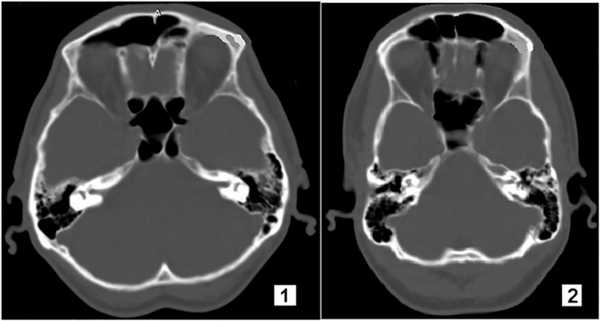

Короткая широкая ЗЧЯ (13 наблюдений из 160, или 8,1%) по сравнению с длиной узкой отличалась более массивной петрозальной частью, ВСК залегал глубже и был короче в среднем на 4,2±0,2 мм. В короткой ямке угол схождения пирамид височных костей был тупой, пирамида смещалась кзади, а вершина внутрь, верхний край пирамиды опускался относительно плоскости верхней грани. В широкой ямке вершина пирамиды смещалась вниз и латерально (рис. 1).

Рис. 1. Различия в строении пирамиды височной кости в короткой широкой (1) и длинной узкой (2) задней черепной ямке.